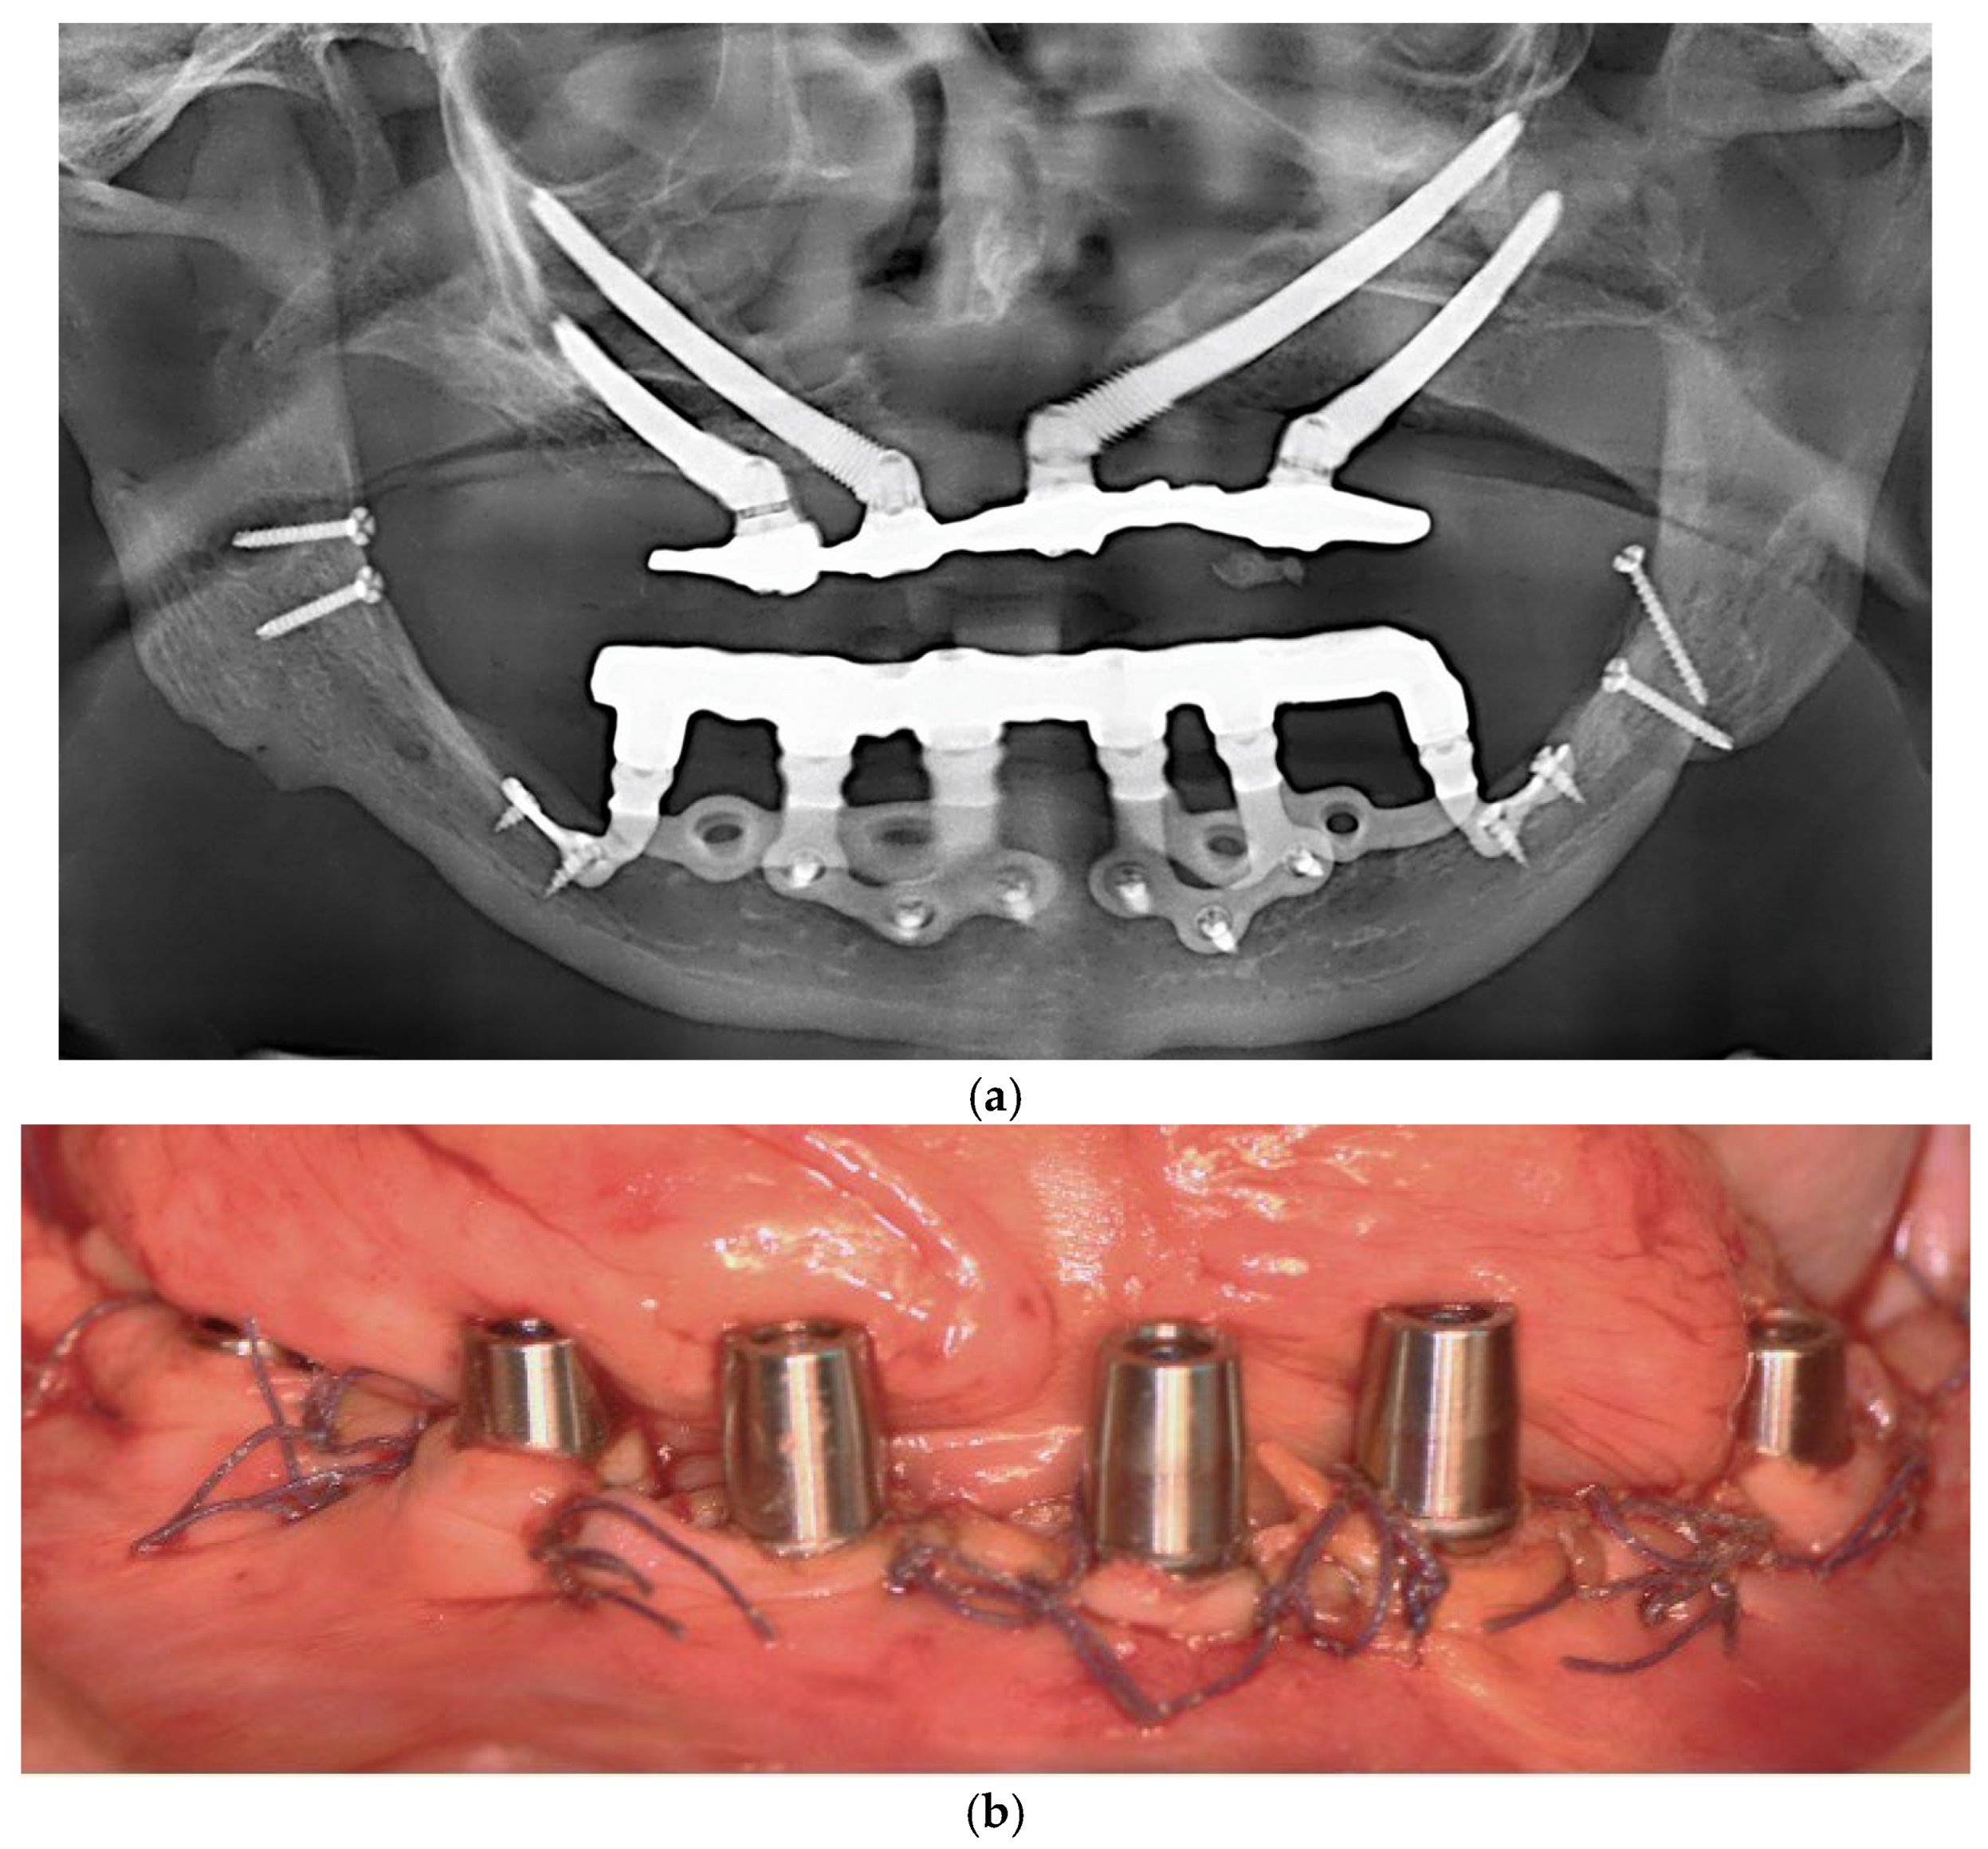

Each subperiosteal implant was passively adapted to the bone and secured with titanium osteosynthesis screws to achieve primary stability (Figure 4).

Figure 4.

Intraoperative view of the mandibular crest showing the placement of subperiosteal implants during surgery.

Flaps were repositioned and sutured with resorbable Vicryl 4-0 sutures. Panoramic radiography and clinical pictures were obtained postoperatively (Figure 5a,b). Within 48 h, digital impressions were taken, and a provisional screwed PMMA prosthesis was delivered. In all patients, immediate loading was achieved without intraoperative complications. Postoperative care included Amoxicillin 1 g twice daily for 7 days, Ibuprofen 600 mg as needed, and Chlorhexidine 0.20% mouthwash twice daily for 14 days. Sutures were removed after 14 days.

Figure 5.

(a) A panoramic radiograph of the patient after subperiosteal implants placement. (b) Intraoral picture of the mandible following subperiosteal implant placement.